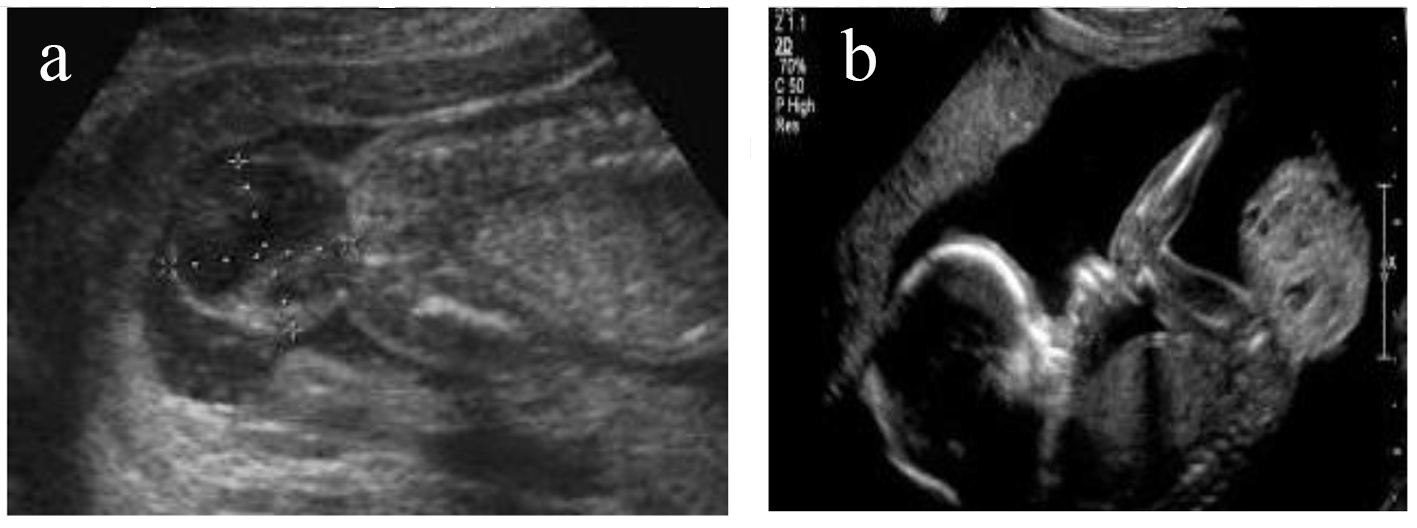

A 24-year-old female patient, first time pregnant, was referred by gynecologist for fetal MRI after ultrasonography examination that showed a mixed, solid/cystic tumorous oval mass in the sacral region of the embryo (Fig. 1a, b). The patient visited our Diagnostic Center “IHC” and accomplished fetal MRI. The technical protocol applied was suitable for embryo-fetal imaging. Multiplanar and multisequential MRI of the fetus was performed without contrast, with attention to the fetal CNS and the result showed a large well-circumscribed mixed, cystic/solid oval mass, originating from the right sacro-gluteal region and projecting into the amniotic cavity, 132 × 110 × 76 mm in size. The mass has a heterogeneous appearance.

![]() Click for large image | Figure 1. (a, b) Ultrasonography examination that showed mixed, solid/cystic tumorous oval mass in the sacral region of the embryo. |